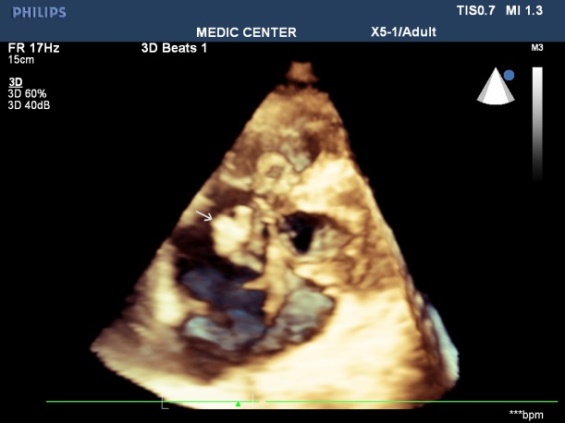

The vegetations in our study have been found on the mitral leaflets with MVP, bicuspid aortic cusps, pulmonary valves and beside small VSD [11-17].

Among 12 cases of Infective Endocarditis, the underlying cardiac lesions includes MVP, Bicuspid Aorta, VSD and pulmonic valve stenosis (Table 2) (Figures 44-51).

Figure 46. Vegetation seen at patient with VSD, 2DTEE imaging

Figure 47. Vegetation seen at patient with VSD, Live 3DTEE imaging